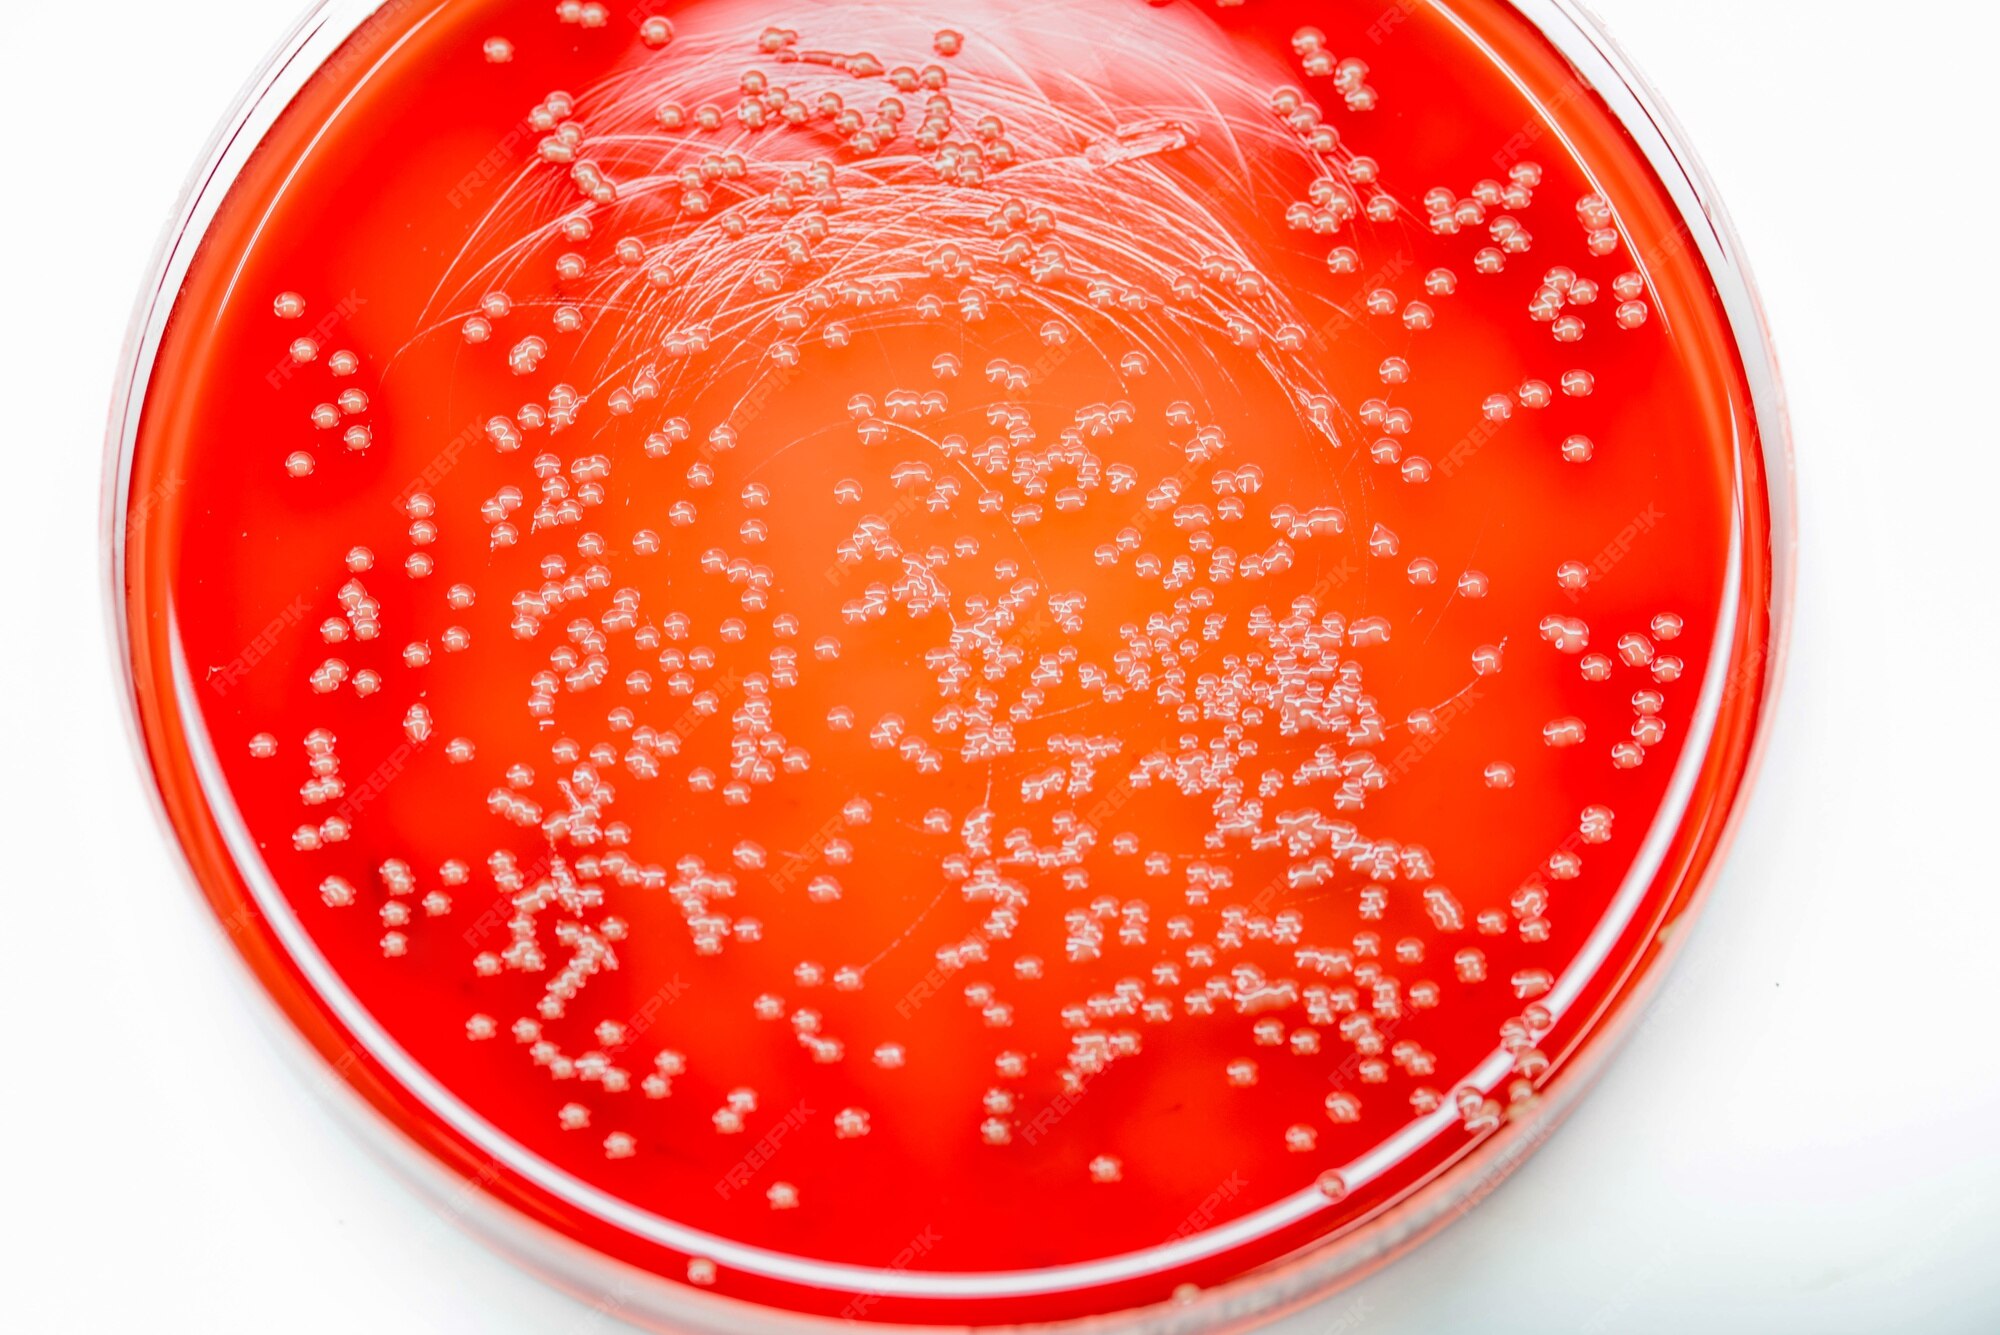

Шигелла Флекснера

Шигеллы дизентерии

Бактерии рода Shigella

Шигелла фото

Shigella dysenteriae микроскопия